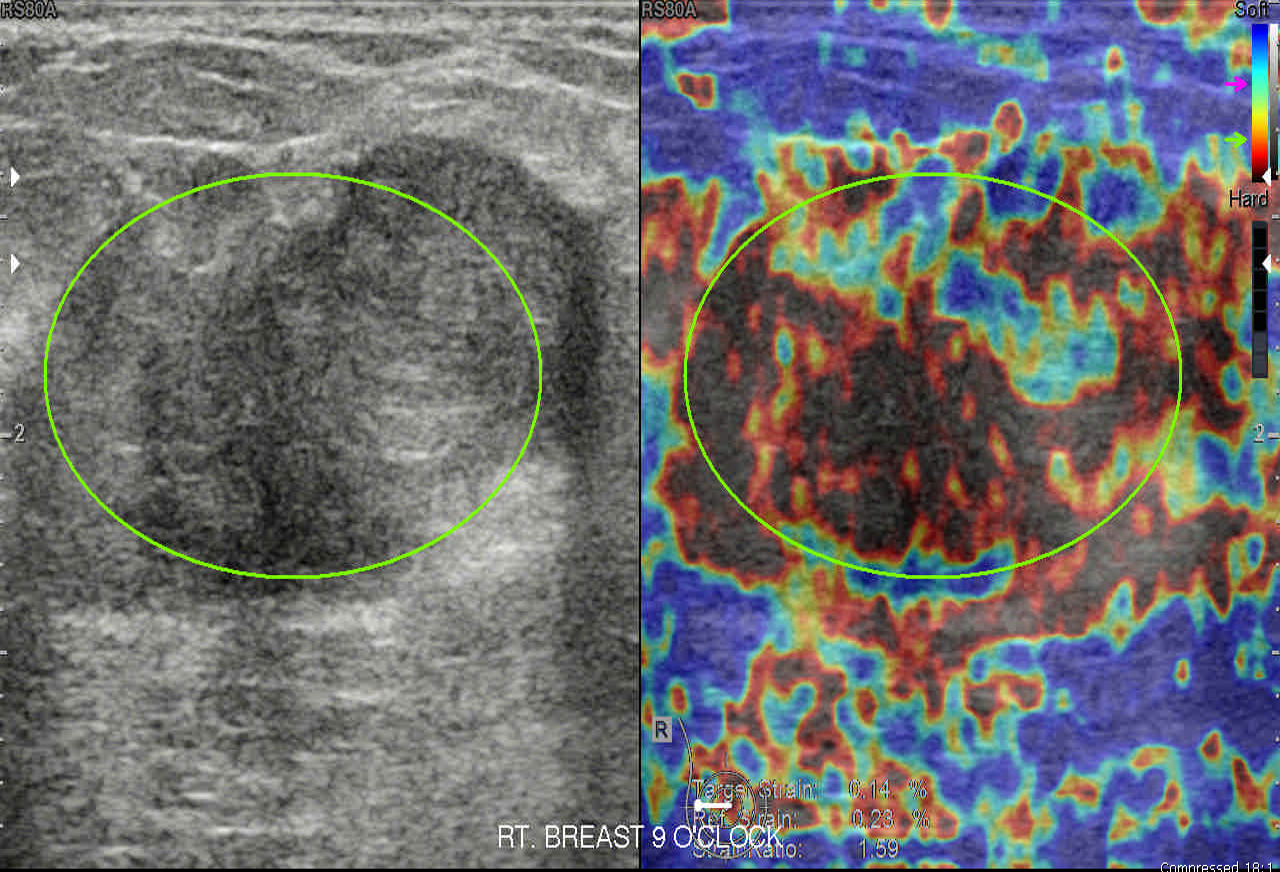

Elastography

Case-167-E1